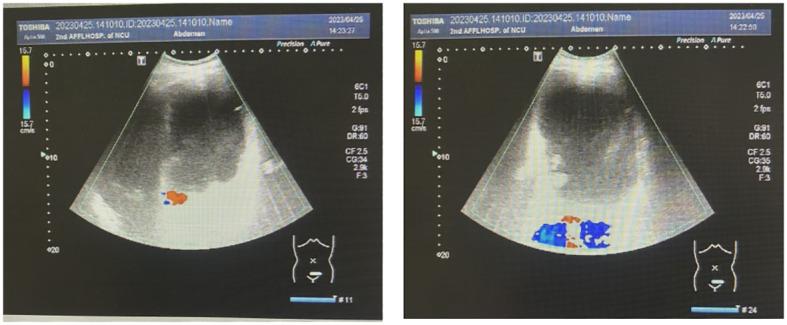

In April 2023, we successfully treated a 21-year-old patient afflicted with a rare giant cystadenocarcinoma, an extraordinarily large mucinous ovarian tumor that weighed nearly 25 kg. The preoperative dimensions of the tumor measured 40 × 30 × 34 cm, with the tumor's weight nearing 25 kg. Despite its uncommon nature, we elected to perform a right adnexectomy, greater omentectomy, and peritoneal biopsy during the surgical intervention due to the patient's youth and the family's expressed desire to preserve fertility. In the subsequent August follow-up, CT scans revealed the complete resolution of the tumor, accompanied by the normalization of tumor markers, indicating a favorable outcome.

2023年4月,我们成功治疗了一名21岁患有罕见巨大囊腺癌的患者,这是一种极其大的黏液性卵巢肿瘤,重达近25千克。肿瘤术前尺寸为40×30×34厘米,重量接近25千克。尽管其性质罕见,但由于患者年轻且家属表示希望保留生育能力,我们在手术干预期间选择进行了右侧附件切除术、大网膜切除术和腹膜活检。在随后8月的随访中,CT扫描显示肿瘤完全消退,同时肿瘤标志物恢复正常,表明预后良好。